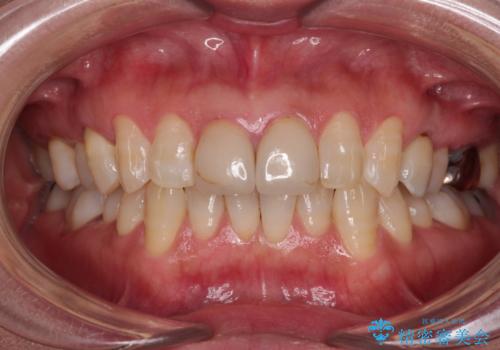

統一感のあるきれいな色調となり、患者様には大変満足していただきました。